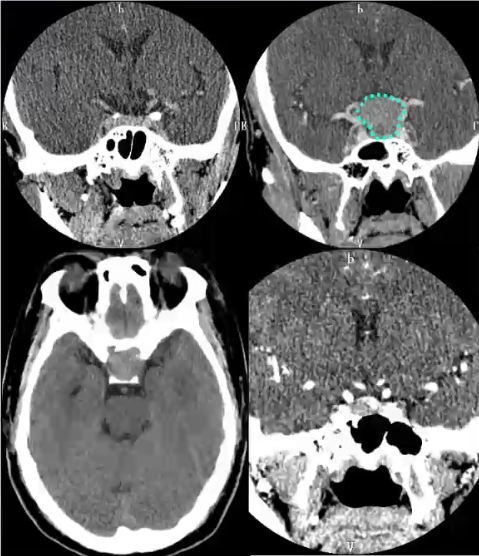

垂体瘤的CT表现:

1)蝶鞍扩大

2)直接征象:鞍内肿块,肿块呈等或略高密度,内常有低密度灶,均匀、不均匀或环形强化。平扫不易显示,增强呈等、低或稍高密度结节

3)间接征象:√垂体高度≥8mm √垂体上缘隆突 √垂体柄偏移 √鞍底下陷